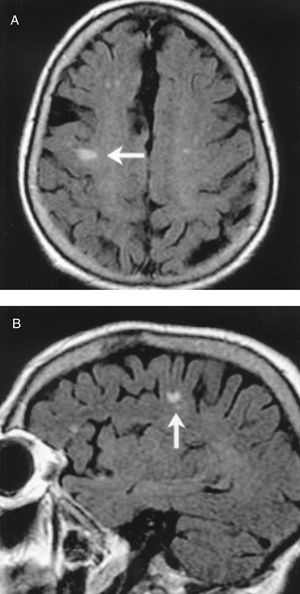

En las primeras 48 h, se realizó un primer estudio de neuroimagen con TC craneal en 50 pacientes. Sólo un estudio mostró hemorragia cerebral, a pesar del potencial riesgo que todos los pacientes sufren por precisar anticoagulación a dosis altas durante el procedimiento quirúrgico y la coagulopatía secundaria al uso de un circuito extracorpóreo. Destaca que, en este estudio inicial, en 35 (70%) pacientes no se observaron hallazgos relevantes que pudieran justificar la clínica. De éstos, en 23 pacientes persistió la clínica neurológica más de 24 h y se realizó un segundo estudio de control para buscar posibles lesiones isquémicas (a los 7-10 días, bien en UCI o planta de hospitalización): 5 estudios demostraron regiones isquémicas coherentes con la clínica; en los 18 restantes, la TC no presentó hallazgos, por lo que también se realizó una RMC. De este último grupo de pacientes, 11 presentaron déficit motor focal; en todos los pacientes, excepto en uno (que clínicamente sólo presentó una disfasia mixta transitoria), en la RMC encontramos áreas de infarto agudo o subagudo en diferentes localizaciones, fundamentalmente de pequeño tamaño, en distribución periférica, en territorios frontera, que podrían justificar los hallazgos clínicos (tabla 1). Estas imágenes aparecen hiperintensas en las imágenes de las secuencias T2 y secuencia FLAIR (secuencia de supresión de líquido cefalorraquídeo). También se realizó RMC en 4 pacientes con encefalopatía leve-moderada y sin hallazgos radiológicos en la TC; de éstos, 1 estudio no mostró alteraciones significativas, pero en los otros 3 se observaron lesiones similares a las descritas previamente en los pacientes con ictus, mostrando lesiones hiperintensas sugerentes de infartos agudos o subagudos. Por último, se realizó RMC en 3 pacientes con una clínica de encefalopatía severa y coma superior a 48 h; en ellos se objetivaron áreas múltiples de infarto a nivel cortical, que aparecieron como una hiperintensidad cortical global, con edema en las circunvoluciones. En las figuras 3 y 4 se presentan ejemplos de RMC en ictus posquirúrgicos, con TC de cráneo sin hallazgos patológicos. En la figura 5 se observa la RMC de un paciente con despertar prolongado y posterior afectación del nivel de conciencia durante aproximadamente 36 h y TC craneal sin hallazgos.

Fig. 5. Sustitución valvular aórtica y revascularización coronaria. Despertar prolongado y posterior afectación del nivel de conciencia durante aproximadamente 36 h y tomografía computarizada craneal sin hallazgos. En la resonancia magnética cerebral se observa una pequeña lesión de bordes definidos en región parietal derecha.